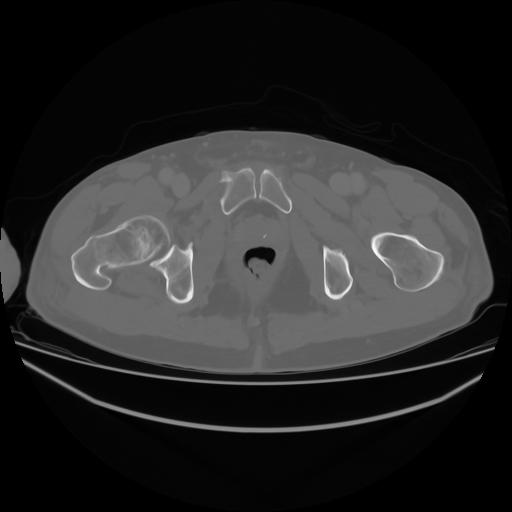

4 CUERPO,CE,Axial,3.0,CUERPO,,